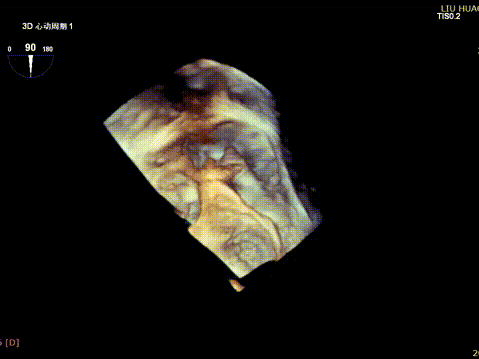

The operation was performed in a hybrid operating room and completed under the guidance of real-time three-dimensional transesophageal echocardiography (3D TEE) and X-ray fluoroscopy throughout the entire process.

3D color Doppler

Mitral valve Zone 2

Color Doppler of Mitral valve Zone 2